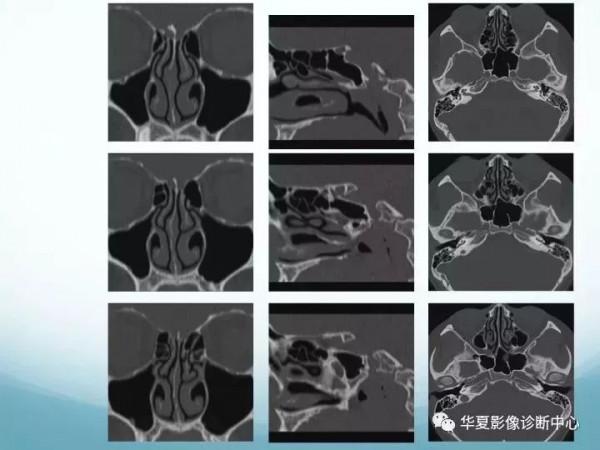

7CT軸位鼻腔和鼻竇層面(蝶竇水平) - 解剖圖片

頭頸五官CT斷層解剖圖及常見病影像診斷

8CT軸位鼻腔和鼻竇層面(中鼻甲水平) - 解剖圖片